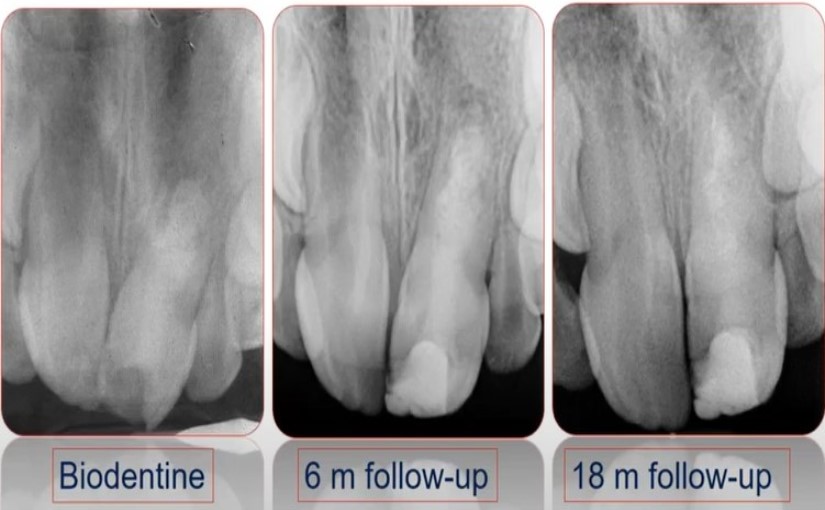

This webinar, sponsored by Septodont, was organised by the Department of Paediatric Dentistry – Ghent University on the occassion of 10 years experience with BIODENTINE.

A story about the treatment of deep caries, reversible and irreversible pulpitis without root canal treatment.